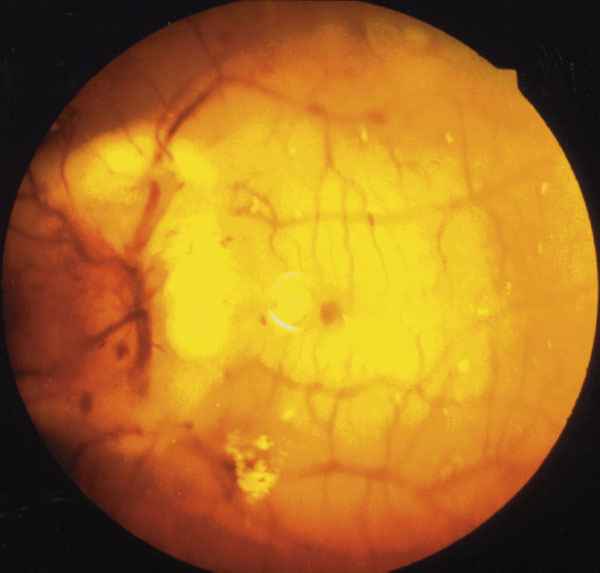

INFILTRACIÓN DEL NERVIO ÓPTICO DE OI. OBSTRUCCIÓN DE LA ARTERIA CENTRAL DE LA RETINA.